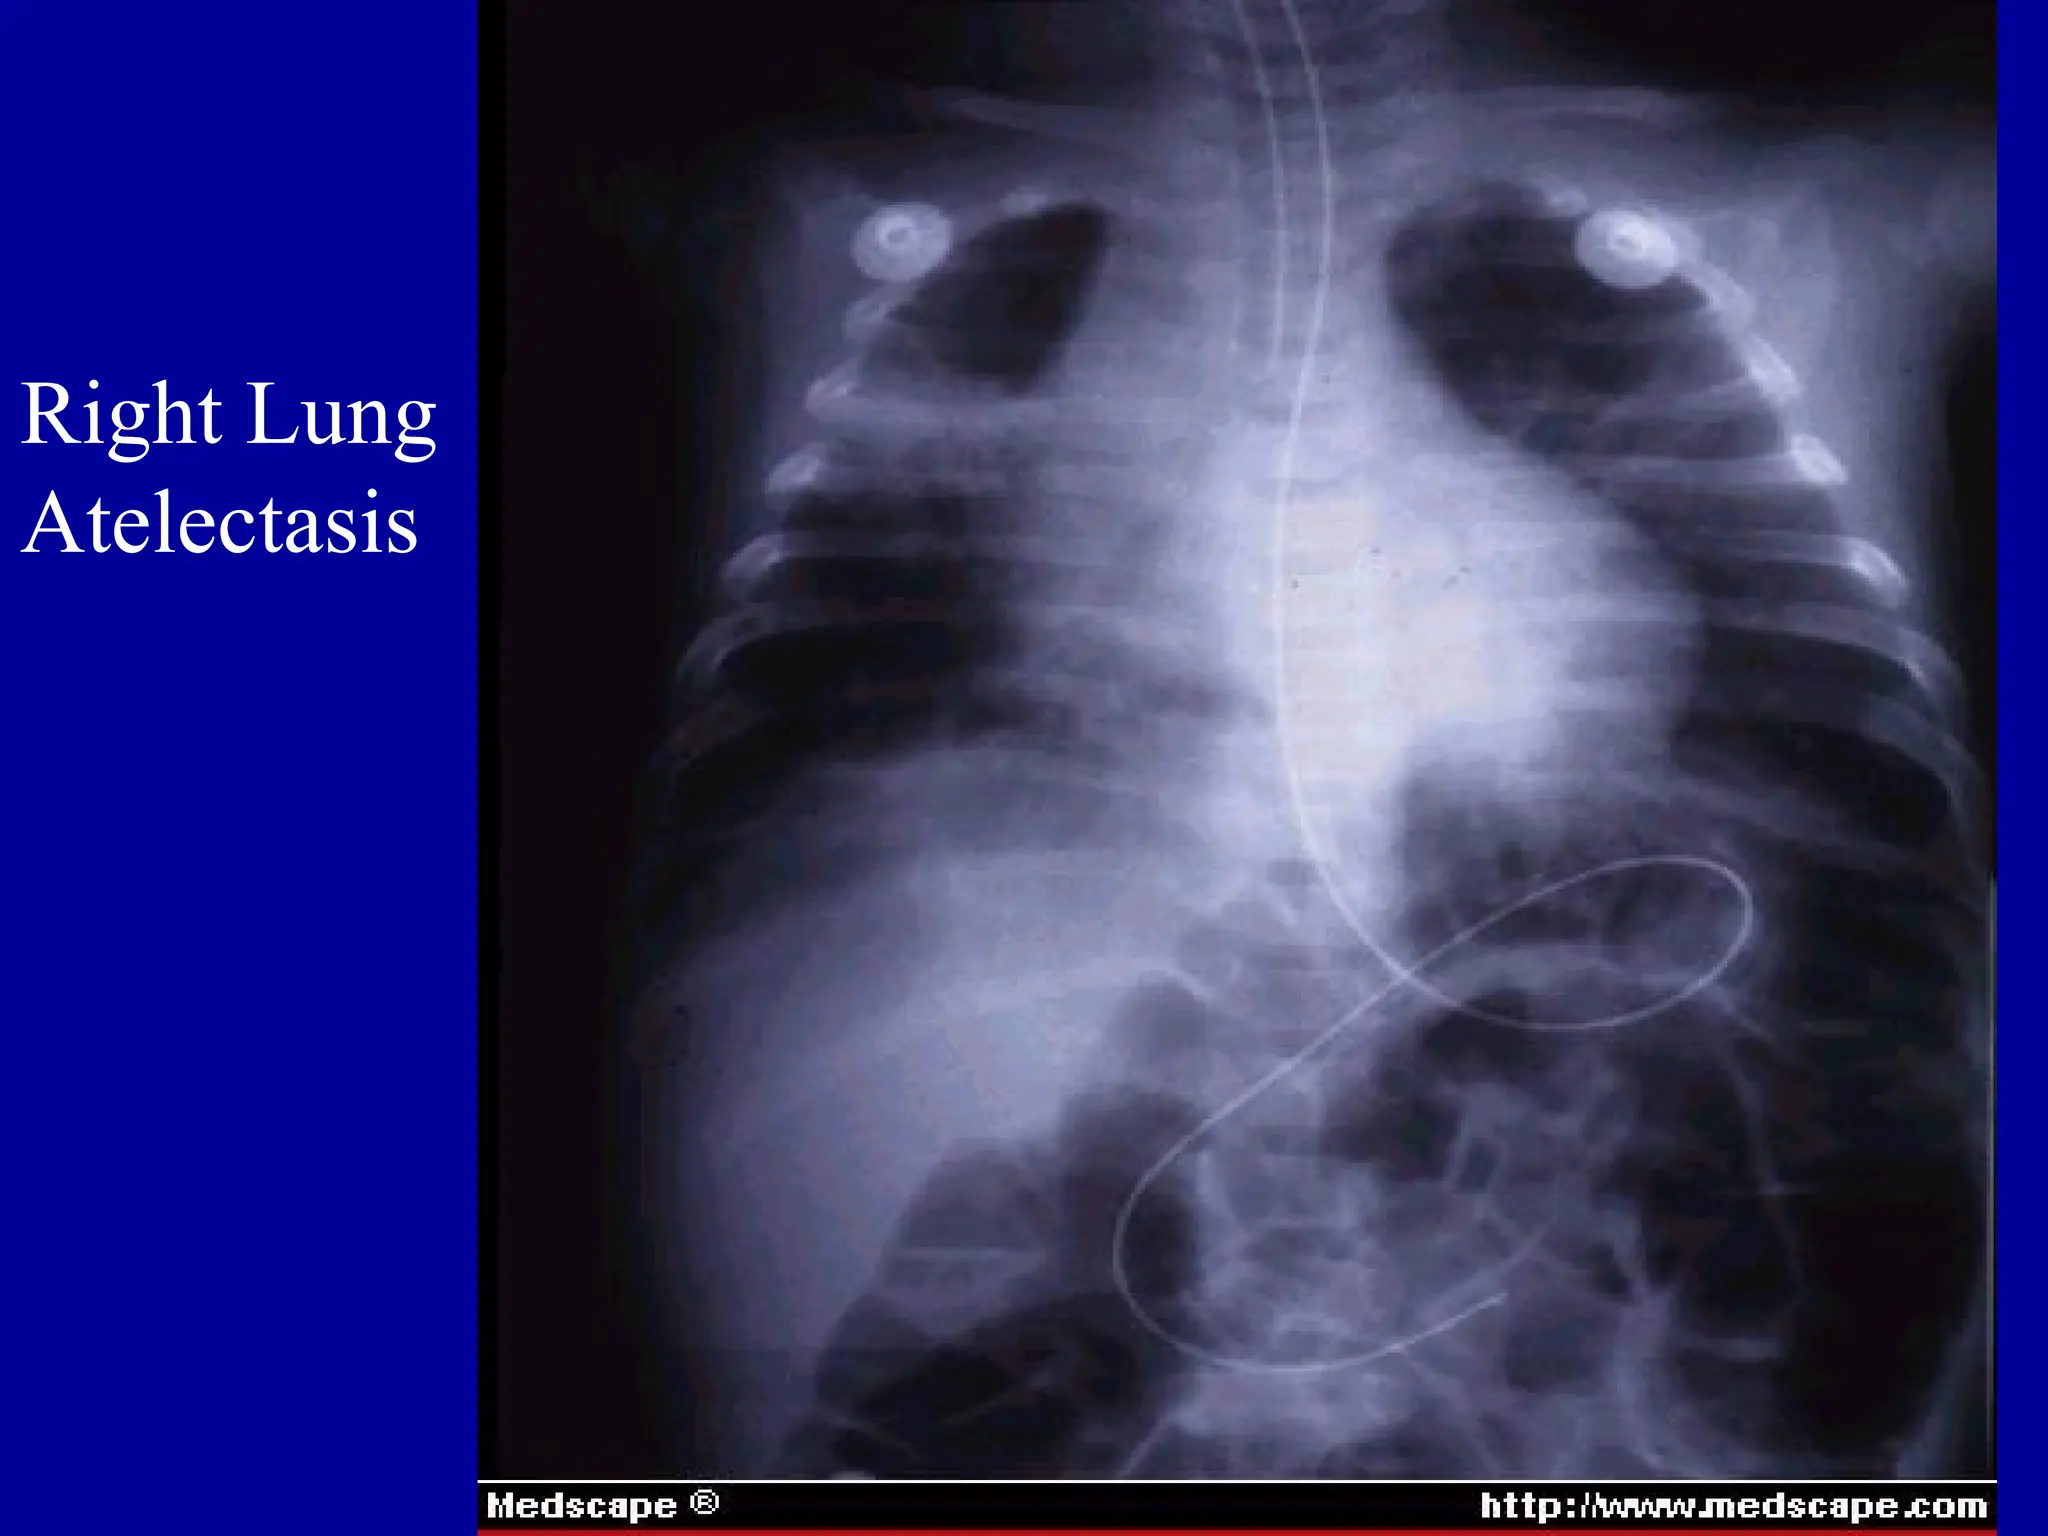

Foreign Body Aspiration

Right Lung

Atelectasis